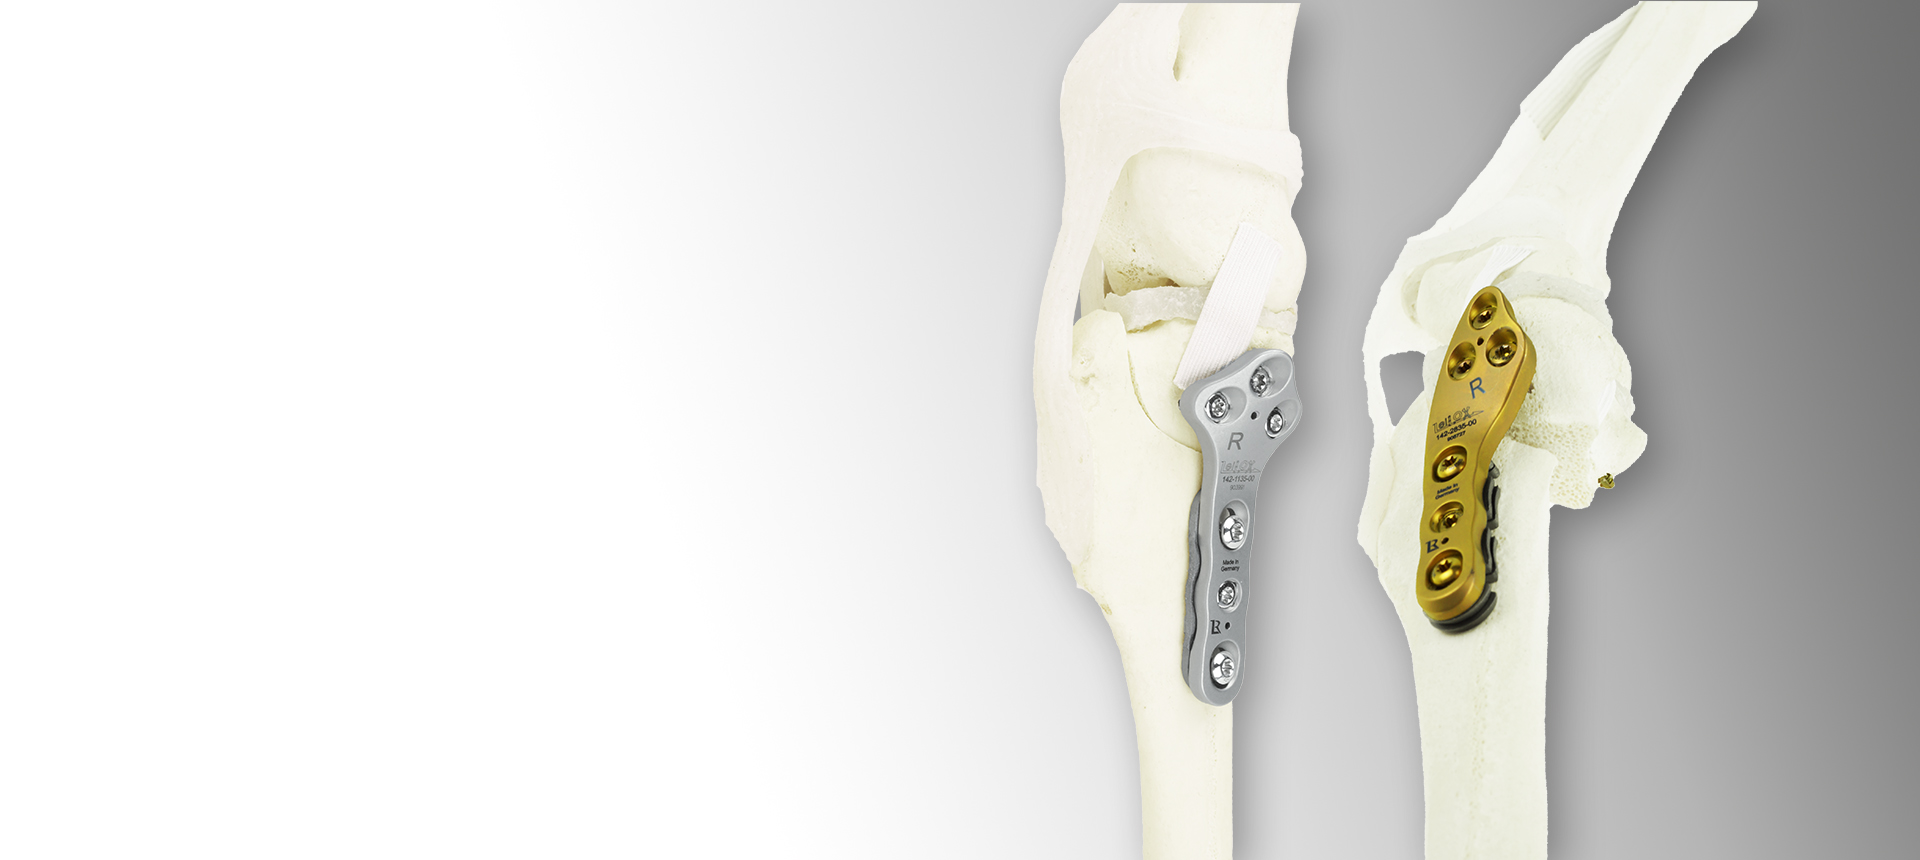

Technology Leading Manufacturing

A Titanium LeiLOX CBLO Plate is born in one of our in-house machines: